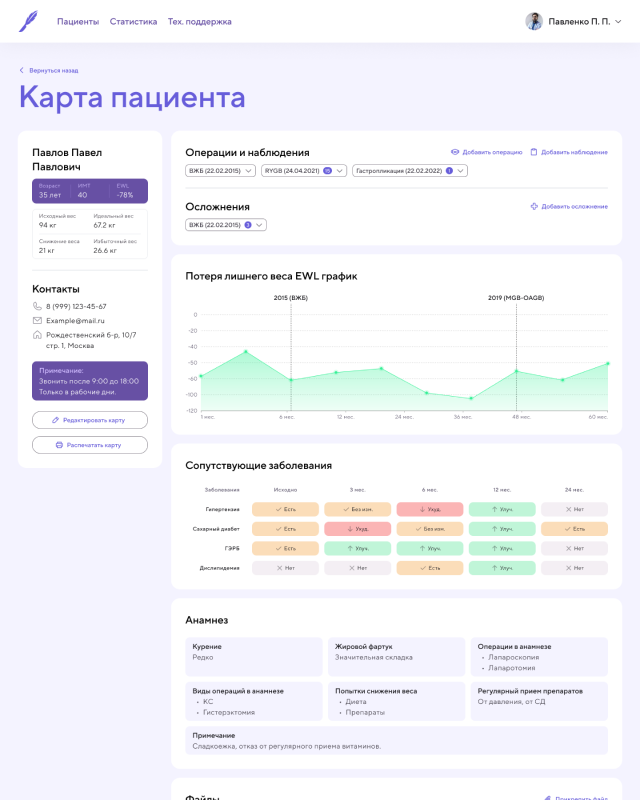

CRM Приложение [ 2022 ]

Работал над CRM-приложением для хирургической клиники по снижению лишнего веса, разработанным с использованием Pug, Vanilla.js и CSS. Приложение предназначено для ведения и учета пациентов, управления операциями и отслеживания результатов лечения.

В рамках проекта реализованы: авторизация и роли пользователей, создание и ведение карт пациентов, продвинутая фильтрация по различным параметрам, а также большие формы для создания операций и наблюдения за пациентами. Для визуализации результатов лечения использовались Chart.js, позволяя наглядно отображать статистику и эффективность применяемых методов.

Я работал над архитектурой интерфейса, реализацией ключевых функций, обеспечением удобного и логичного взаимодействия с данными, а также над оптимизацией форм и графиков для комфортной работы медицинского персонала. Приложение получилось функциональным, наглядным и удобным инструментом для управления пациентами и анализа результатов клиники.